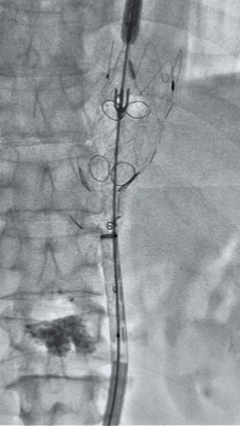

6. 解除束径,打开近端后释放,经肱动脉长鞘超选支架外分支,并进一步超选右侧肾动脉,交换加硬导丝,送入覆膜支架6*50mm和7*60mm各一枚,并予以球囊后扩张,手推造影显影良好。

7. 经长鞘重新选入左侧外分支,并超选进左肾动脉,沿导丝送入外周血管覆膜支架7*60mm一枚,并予以球囊后扩张,手推造影显影良好。

8. 从右侧股动脉入路送入腹主支架AB-24-12-110-S,近端重叠胸腹主动脉支架远端,调整好支架位置后释放。